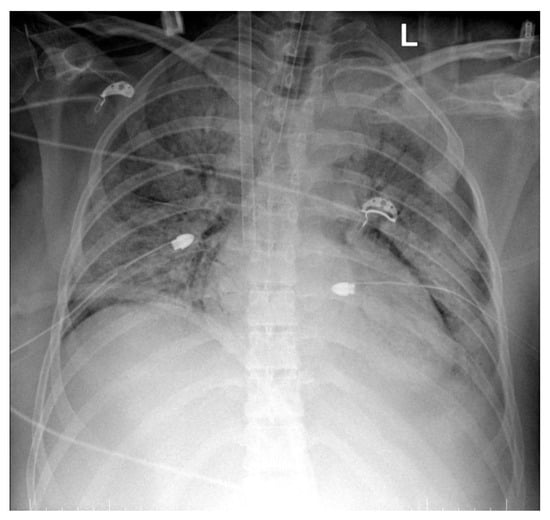

- Quasi-complete resorption of pulmonary condensation foci and, respectively, reduction in pleural effusion bilaterally. Lungs with increased transparency. ECMO cannula at the level of the right internal jugular vein.